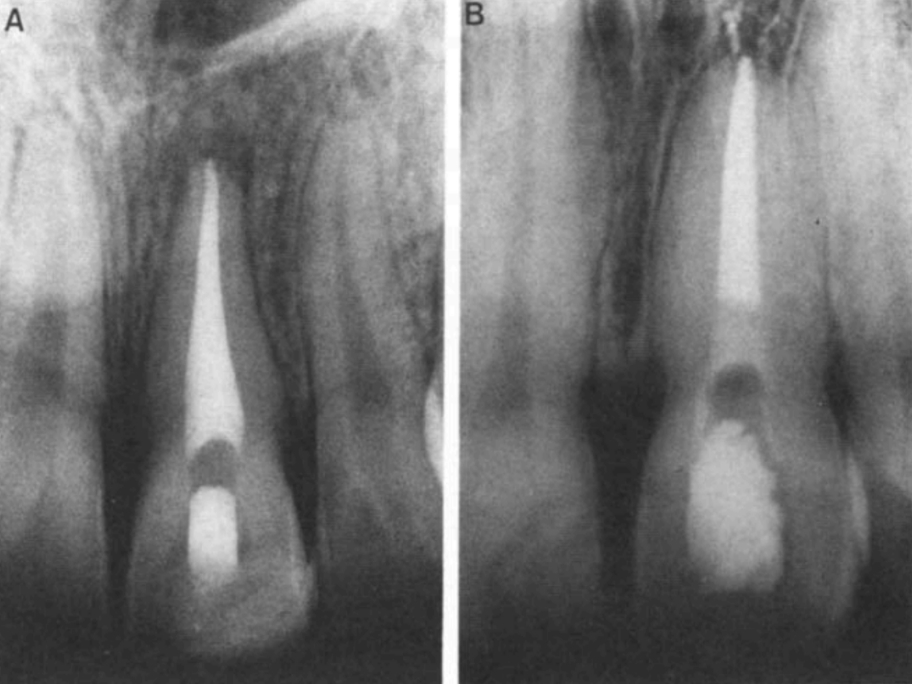

Рис. 5. Вид барьера на рентгенограмме. А - барьер с использованием Cavit. Б - барьер из стеклоиономера.